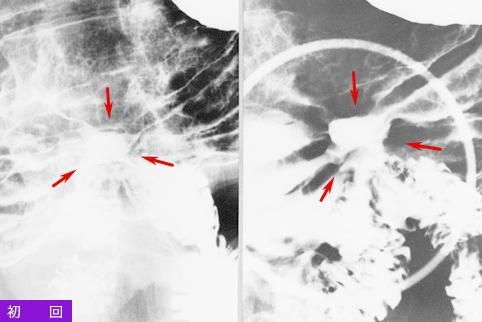

clasificación del pacienteTumor Epitelial Maligno/Adenocarcinoma

parte(separada por órganos)estómago(región)/cuerpo

método de exámenRayos X

clasificación ectoscópica de tumoresTipo 0(tipo superficial)/Tipo III(III+IIc)

diámetro mayor del tumor20 - 24

grado de penetraciónm